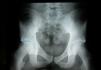

De cintura pélvica en dirección caudal observamos: articulación coxofemoral (coxometría radiológica [fig. 1]). Plano sagital: ángulo de cobertura anterior aumentado; plano frontal: ángulo superoexterno Wiberg aumentado. Ángulo superointerno disminuido. El ángulo de inclinación del techo se aproxima a 0°.

En el plano horizontal podemos analizar que la orientación anatómica del cuello femoral se inclina aproximadamente 135° cranealmente. Verticalmente se inclina 10-25°, obteniéndose así el valor del ángulo de anteversión del cuello femoral. La existencia del ángulo de Wiberg aumentado y del ángulo de inclinación del techo disminuido nos confirma una cadera penetrante4,5.